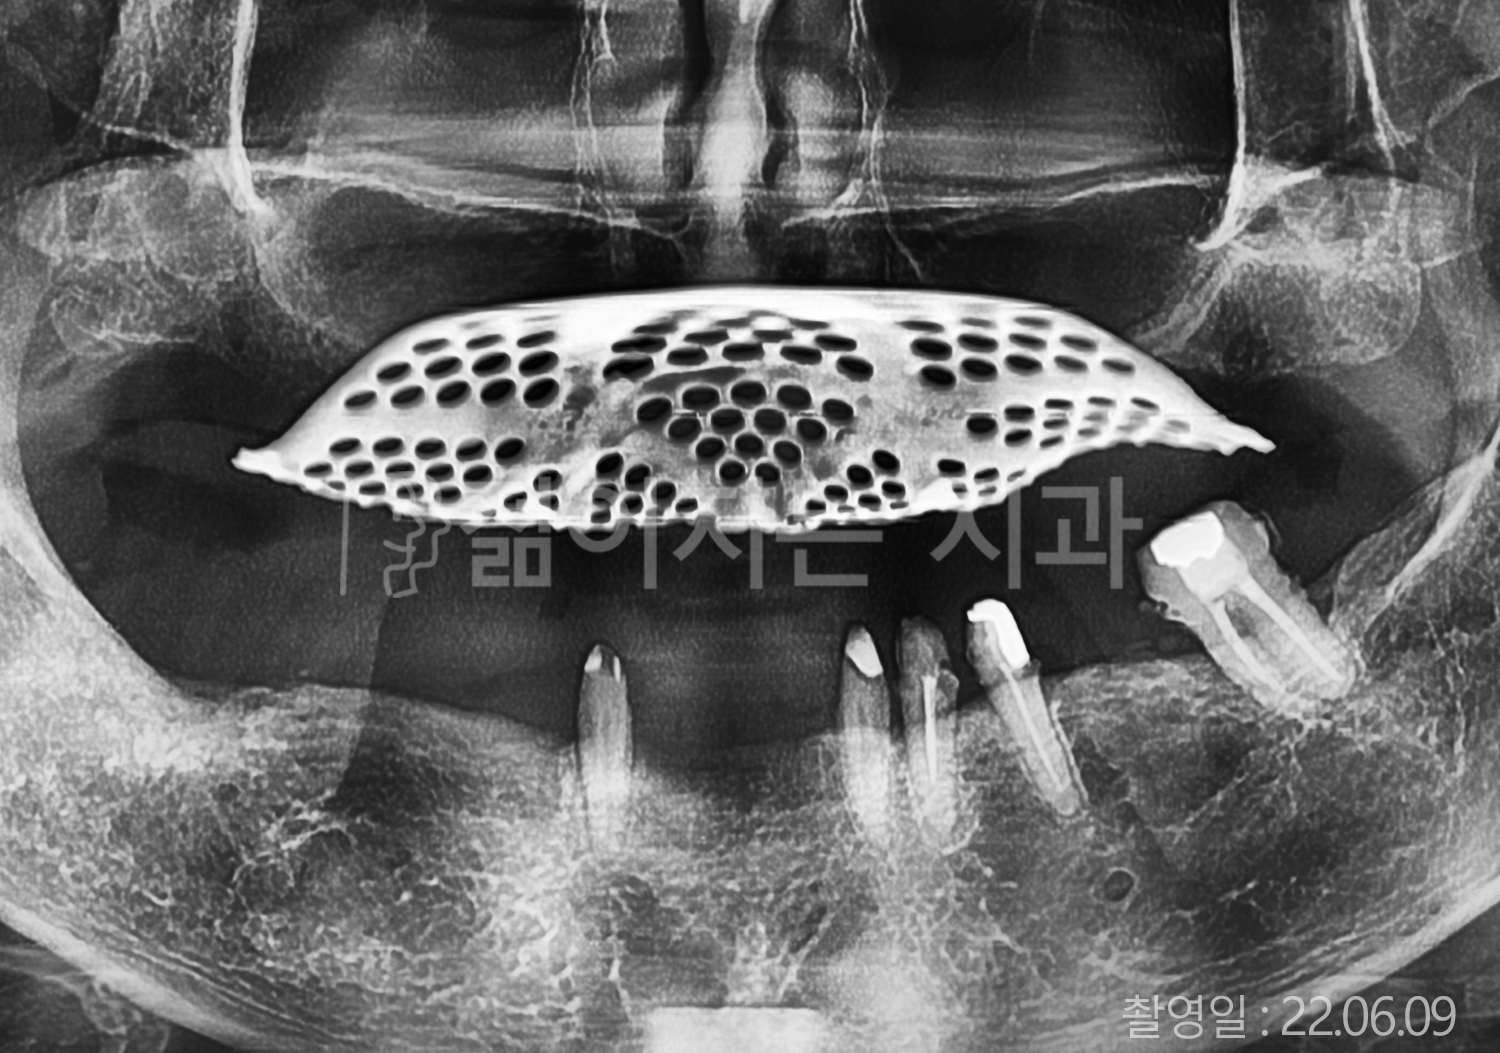

• 50대 전체치아 10개 이상 임플란트